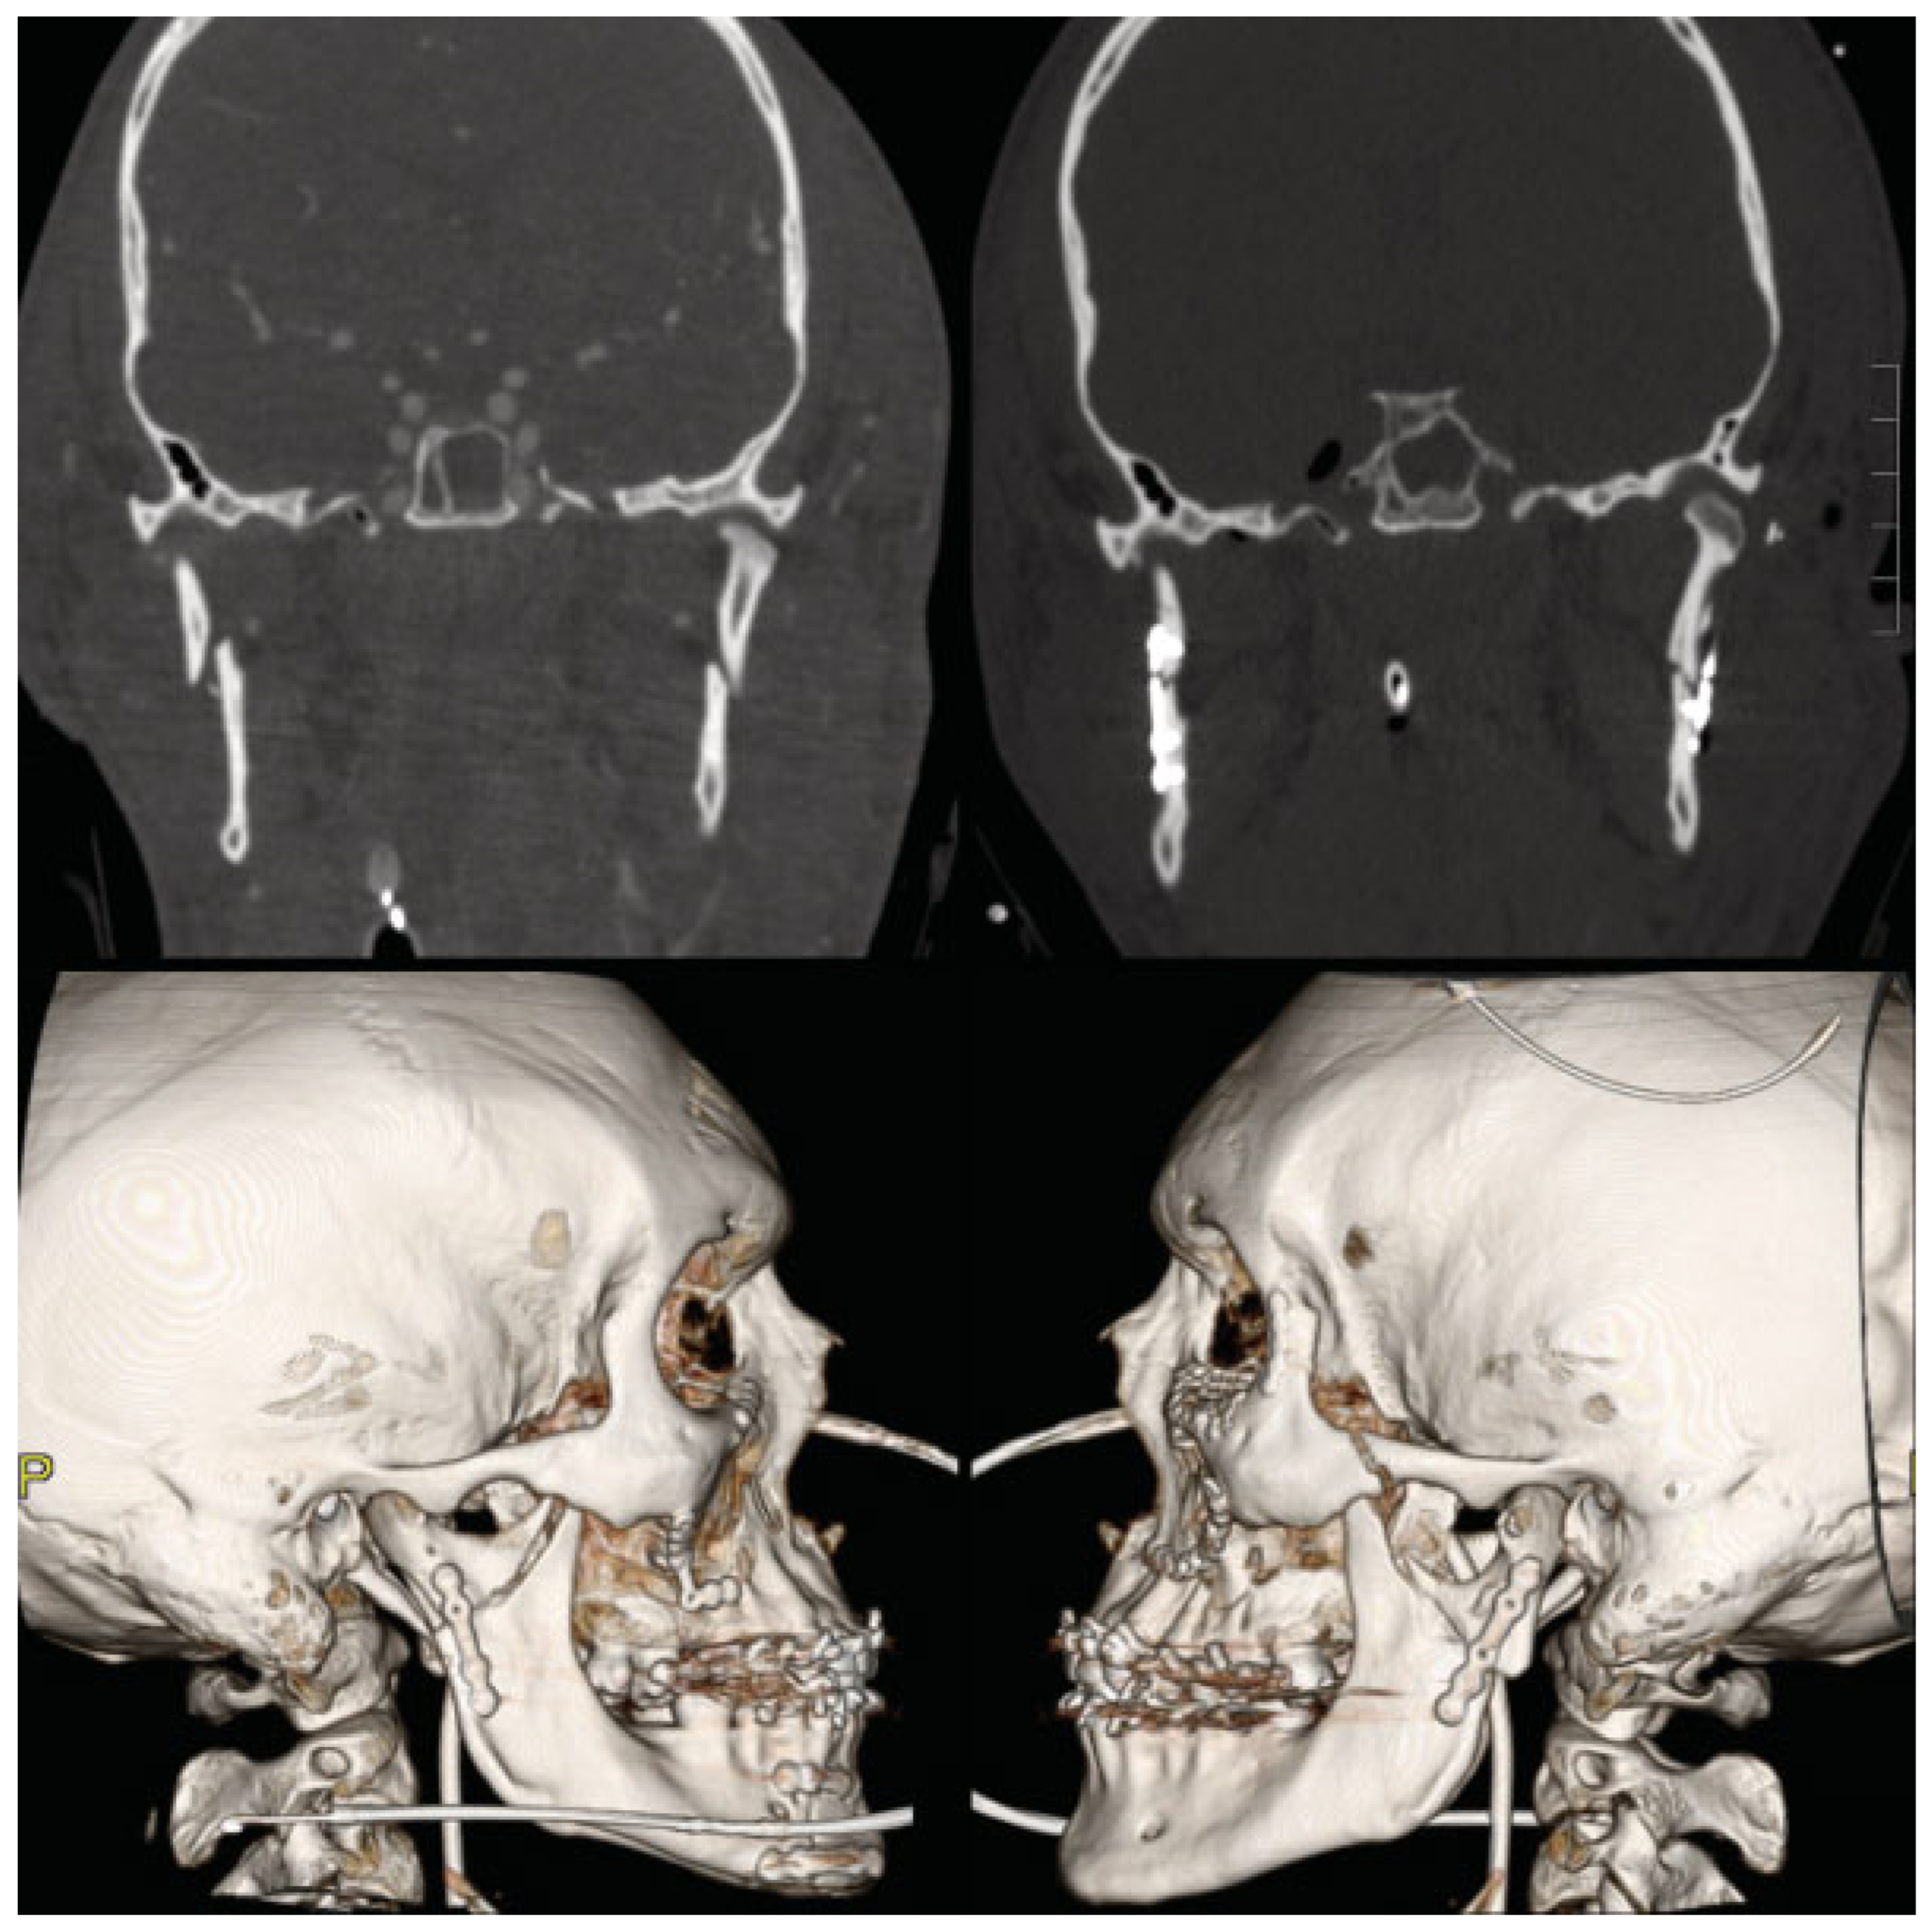

Case 3: Bilateral ORIF of Type III Injury

A 25-year-old man was in a motor vehicle crash and was admitted for multiple facial fractures including left zygoma- ticomaxillarycomplex, left orbital floor, bilateral Le Fort I, right parasymphyseal, and bilateral subcondylar (type III) fractures (Figure 4). He underwent ORIF of his extensive midface and mandible fractures. Open treatment of both subcondylar fractures was performed through retromandibular approaches to reestablish occlusion and posterior facial height. The patient was kept in wired IMF for 10 days and then transitioned to guiding elastics. He had pain in bilateral TMJ areas which eventually resolved at approximately 6 weeks after the injury. At that time, the arch bars were removed and patient had achieved MMO of 42 mm with normal occlusion.

Figure 4. Type III bilateral condylar injury managed with bilateral open reduction and internal fixation (ORIF). CT imaging of a patient with bilateral subcondylar fractures after fall (above left). Postoperative imaging after ORIF of bilateral subcondylar, right parasymphyseal, and extensive midface fractures (above right and below).